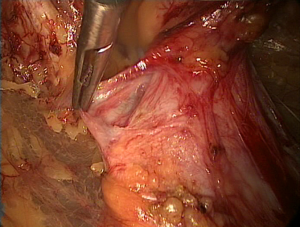

The transverse fascia in the lower anterior abdominal wall is divided into two layers (Figure 4). The superficial transverse fascia tightly covers the inner surface of the anterior abdominal muscles, but it is thin and has no clinical value in a hernia repair. The deep transverse fascia, beneath the superficial transverse fascia, covers the parietal peritoneum and is relatively thick and dense in 50% of patients (i.e., it is thin and loose in the other 50% of patients). The space between the superficial and deep transverse fascia is the parietal space. The superficial and deep transverse fasciae extend to the inguinal region and cover the blood vessels under the abdominal wall (both sides). Then, they blend with the anterior abdominal wall at the site lateral to the inferior epigastric blood vessels. The lateral transverse fascia continues to ascend to the posterior lower edge of the inguinal ligament and then blends with the iliac fascia. The medial transverse fascia is attached to the pubic bone, the pectineus muscle and Cooper’s ligament. The deep transverse fascia becomes a funnel-shaped structure that extends downward to cover the spermatic cord structures (the vas deferens, the testicular vessels and the hernia sac of the oblique inguinal) at the internal inguinal ring and becomes the internal spermatic fascia entering the inguinal canal. Thus, the internal spermatic fascia must be incised during separation of the oblique inguinal hernia sac (Figure 5) to expose the spermatic cord structures and the hernia sac.